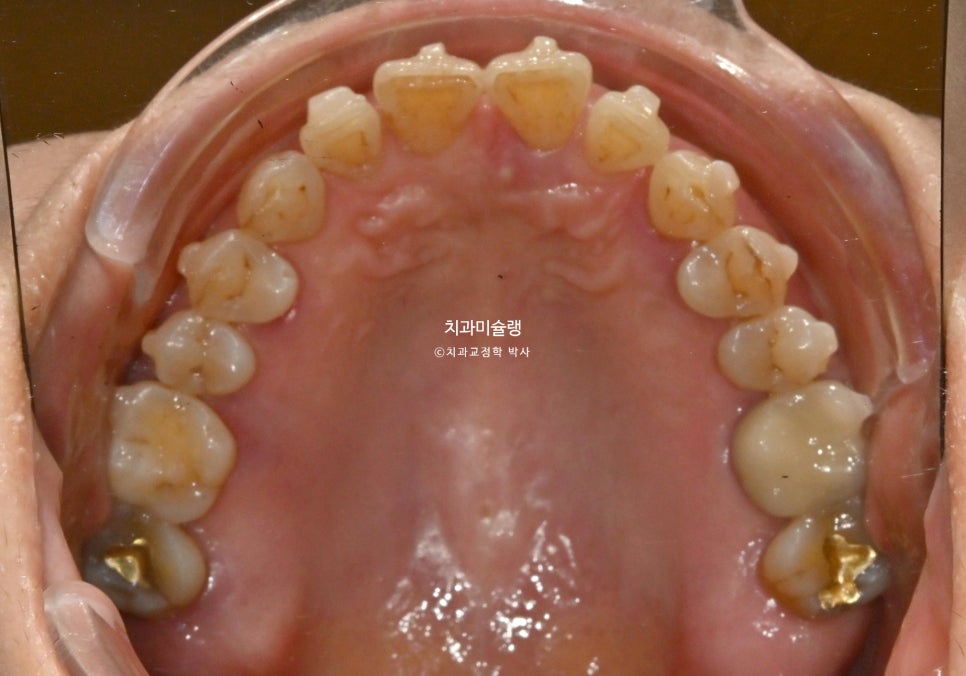

앞니 사이 블랙트라이앵글이 여기저기 보입니다.

측면 사진에서 앞니 사이의 벌어진 큰 틈이 잘 보입니다.

앞니들이 벌어진것 뿐만 아니라 회전된, 소위 “나비치아”입니다.

그에비해 아래앞니는 틈도 없고 틀어짐도 경미하죠.

어금니는 배열이나 교합상 문제가 없습니다.